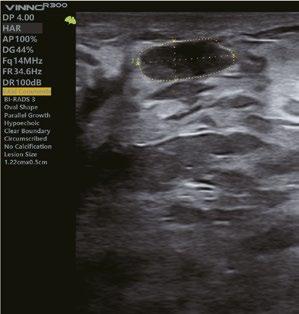

Schilddrüse

Schilddrüsenknoten werden mit dem TI-RADSKategorisierungs- und Berichtswerkzeug in Echtzeit oder auf gespeicherten Bildern erkannt, wodurch die klinische Routine der Schilddrüsen-Ultraschalluntersuchung genauer und produktiver wird.

Automatisches Brustscreening und Läsionserkennung in Echtzeit oder gespeicherten Bildern, zusammen mit der intelligenten BI-RADS-Analyse, verbessert effektiv die Qualitätskontrolle.